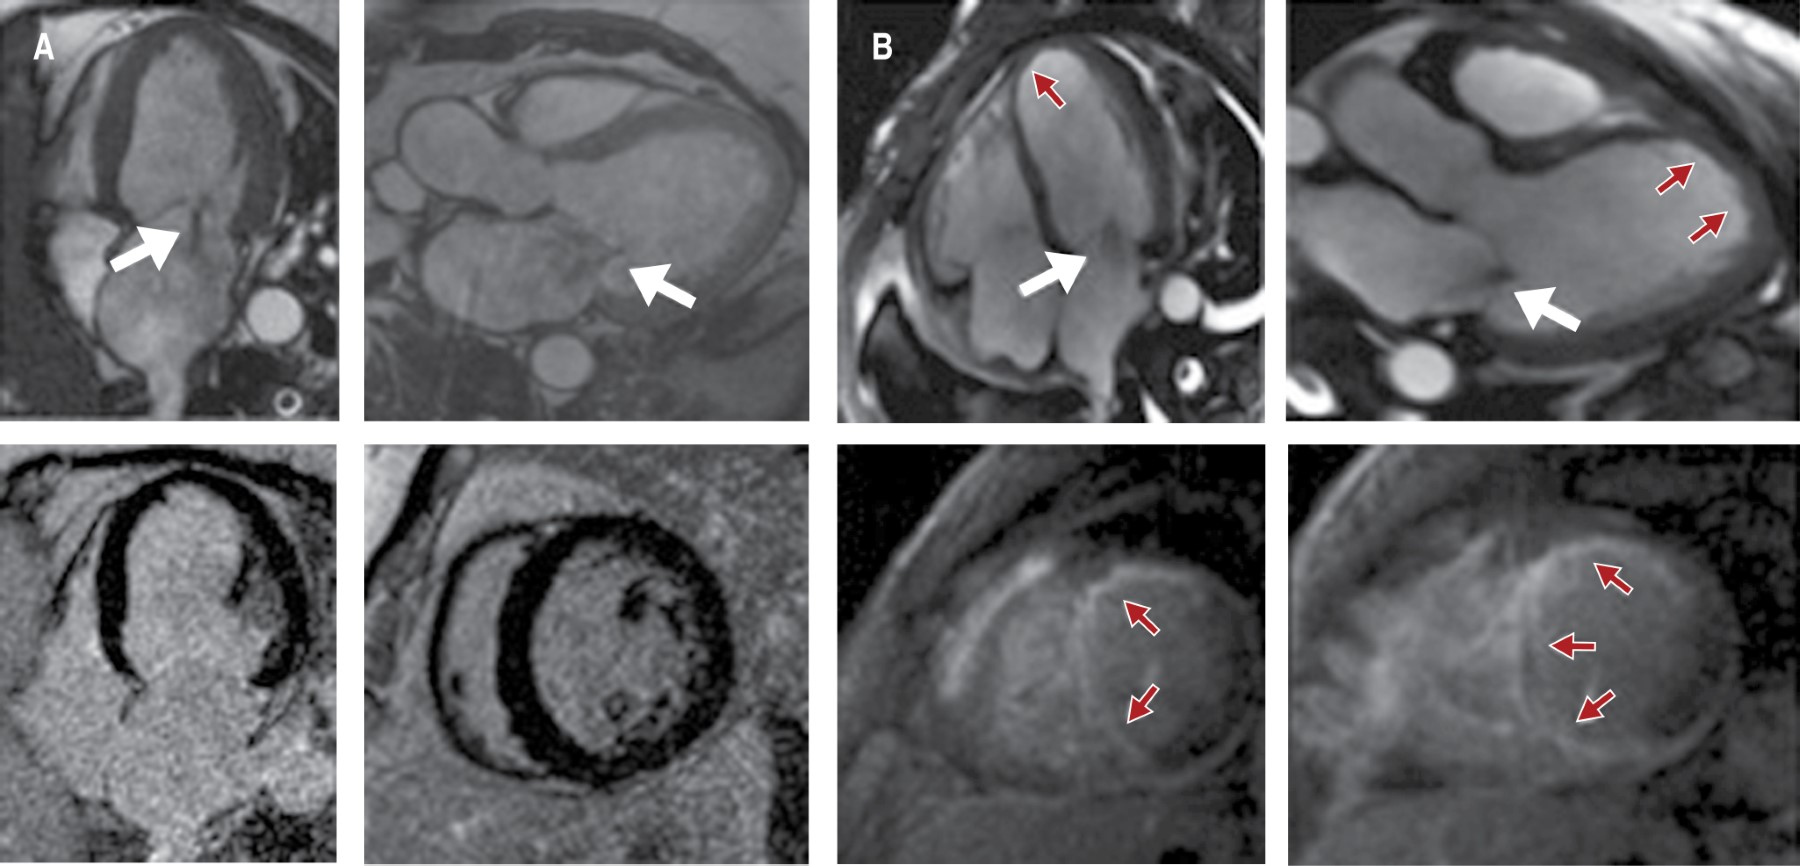

Figura 1